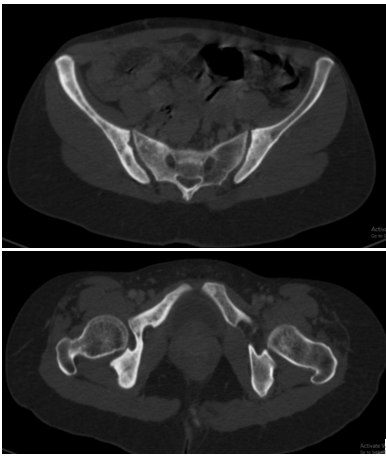

Hình 6, 7: Hình ảnh đặc xương không đều cánh chậu 2 bên.